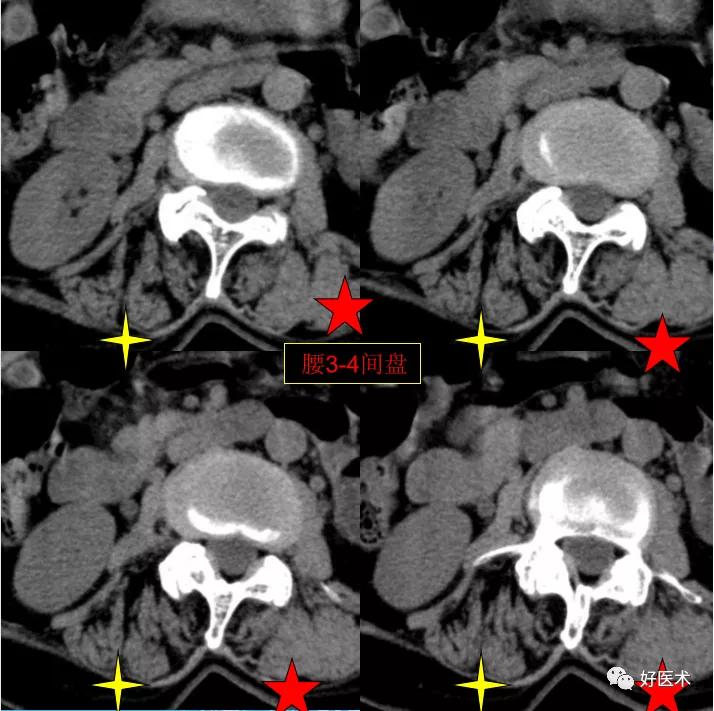

CT图像,腰椎常规采用序列扫描,腰椎体2层,腰间盘4层,层厚2.5mm,一般扫描范围包括腰2--骶1椎体及所属间盘。

腰3-4间盘膨隆。

发现了什么?左侧竖脊肌较右侧明显肿胀饱满, 肌间脂肪间隙消失!!